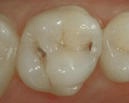

Ett mindre hål